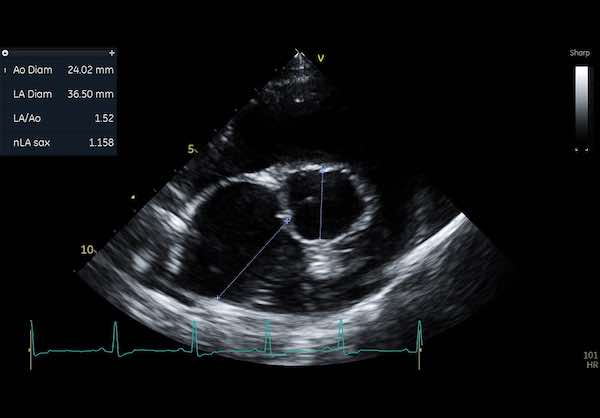

Image: Turbulent flow on colour doppler interrogation of a dog's aorta

🩺 Echocardiogram (ECG): This is an ultrasound of the heart and is one of the best ways to see how well your dog’s heart is functioning.

An echocardiogram is typically the most informative test and provides detailed images of the heart’s structure and function.

While on an echocardiogram you can measure all the internal chamber sizes to fractions of a millimetre.